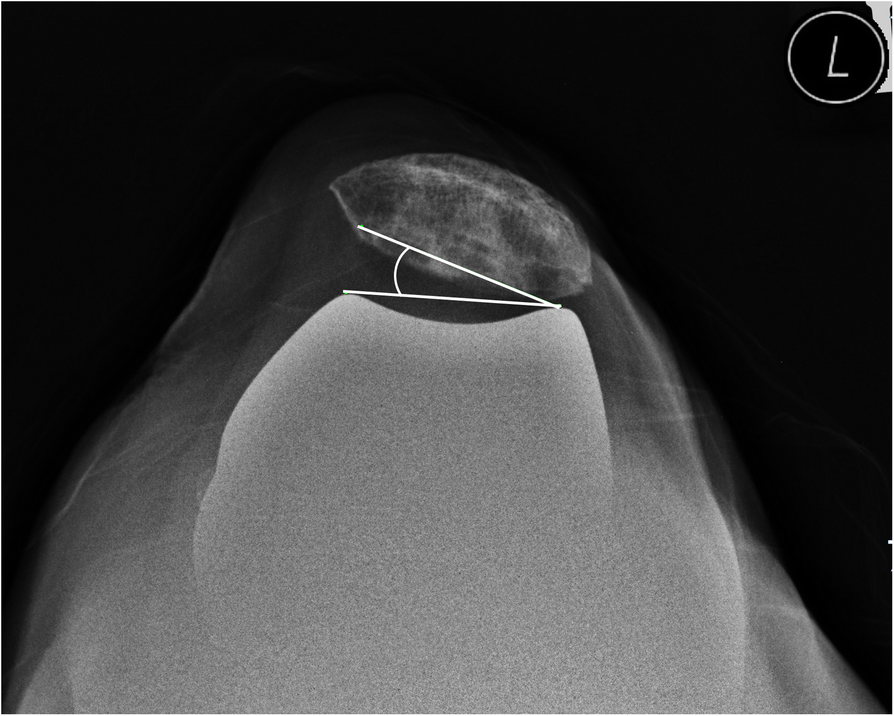

Fig. 4From: Intraoperative patellar maltracking and postoperative radiographic patellar malalignment were more frequent in cases of complete medial collateral ligament release in cruciate-retaining total knee arthroplastyA skyline axial-projection radiograph shows lateral patellar tilt of 16.8° corresponding to patellar maltrackingBack to article page